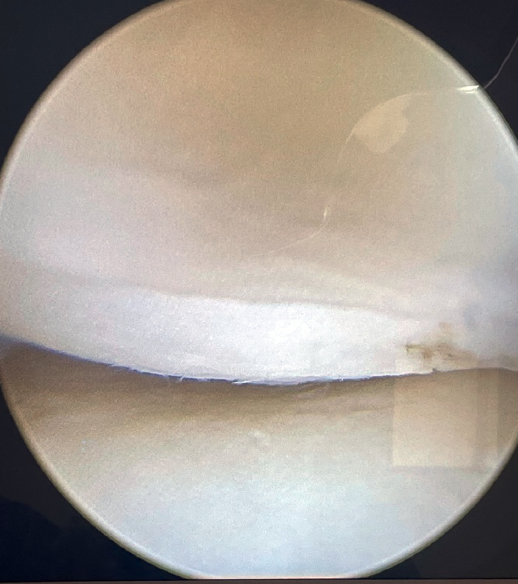

Visioning for lateral complex plication is made through the posterolateral portal. From this portal we access the lateral elbow groove to visualize the posterior part of the radiocapitellar joint. It will also allow us to examine the Osborne-Cotterill lesion component and determine the degree of posterolateral instability by applying varus and supination to the forearm. With this maneuver we can observe how the radial head undergoes subluxation posteriorly and the joint line opens (Figure 2).

If tension is now applied to both sutures and we observe from the posterolateral portal, the radiocapitellar joint is seen to close following plication (Figure 8).